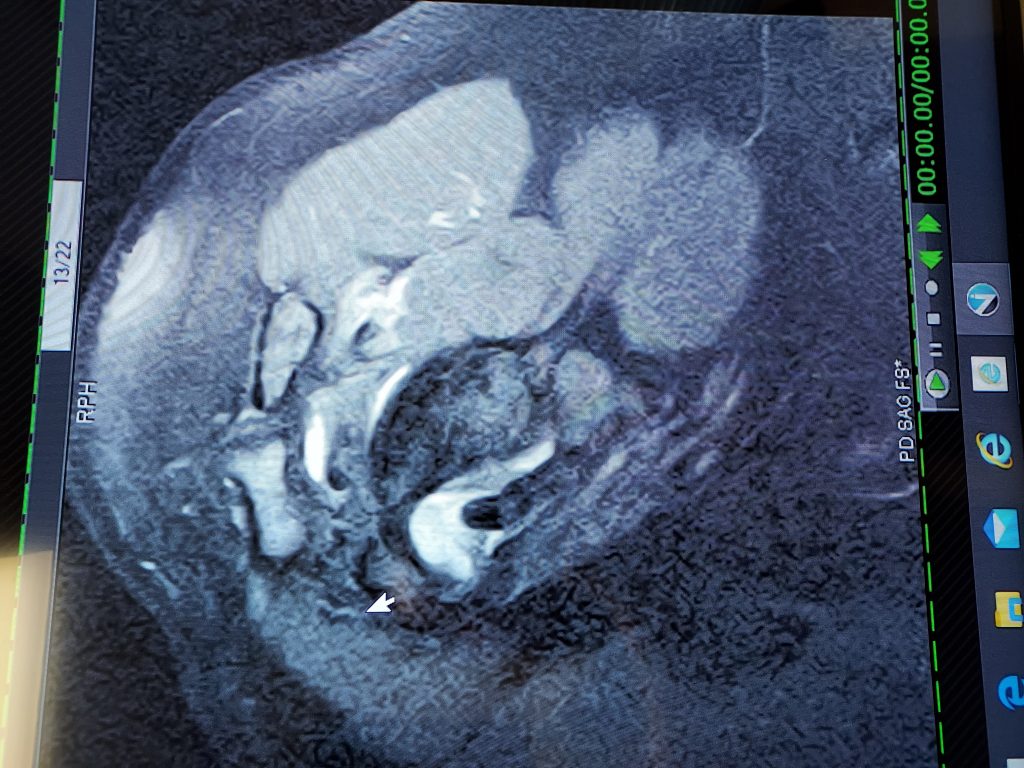

I had arthroscopy surgery on 3/1/23 performed by a surgeon from a different group. He did an amazing job repairing my torn rotator cuff, but unfortunately it did not hold probably due to me going back to lifting weights. I decided to seek out Dr Ryan Simovitch at HSS Florida as he performed extensive rotator cuff and biceps surgery on me in 2018. Dr. Simovitch repaired my rotator cuff, which was torn worse that my 1st surgery. My biceps, labrum, and bursa were also damaged. To say the care and concern shown to my by Dr Simovitch, his his team, and the HSS Florida staff was exceptional would be an understatement. Dr. Simovitch is by far the best shoulder surgeon in the country - maybe even the world in my opinion! He did an amazing job. I've had 33 surgeries and many skilled surgeons, but Dr Simovitch is in a class all by himself. Thank you so much. A debt of gratitude and appreciation.